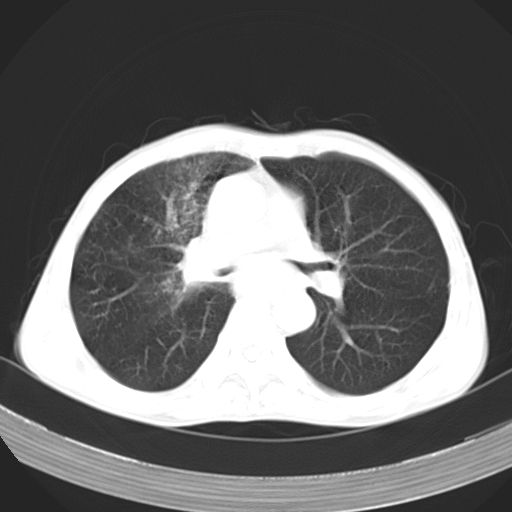

以下是引用苯小孩在2007-5-24 12:47:00的发言:[br]右侧肺门处不均匀密度软组织块影,远端肺组织见斑片模糊影,纵隔内淋巴结明显肿大,边界不清.<纵隔窗第12层面支气管内似见软组织结节>[br]考虑:1、右侧中央性肺癌并阻塞性肺炎并纵隔淋巴结转移可能性大.建议强化或纤支镜进一步检查.[br]2、隆突下淋巴结肿大/食道病变?请做鉴别检查.

以下是引用zhangzhongshou在2007-5-24 12:55:00的发言:[br]1、右肺中叶中心型肺癌并右肺门、隆突下、纵隔淋巴结转移。右肺中叶阻塞性肺炎。

以下是引用jw-830在2007-5-24 15:24:00的发言:[br][br] [br] 考虑右肺中央型肺癌并阻塞性炎症,右肺门及纵隔淋巴结转移。 [br] [br][br]